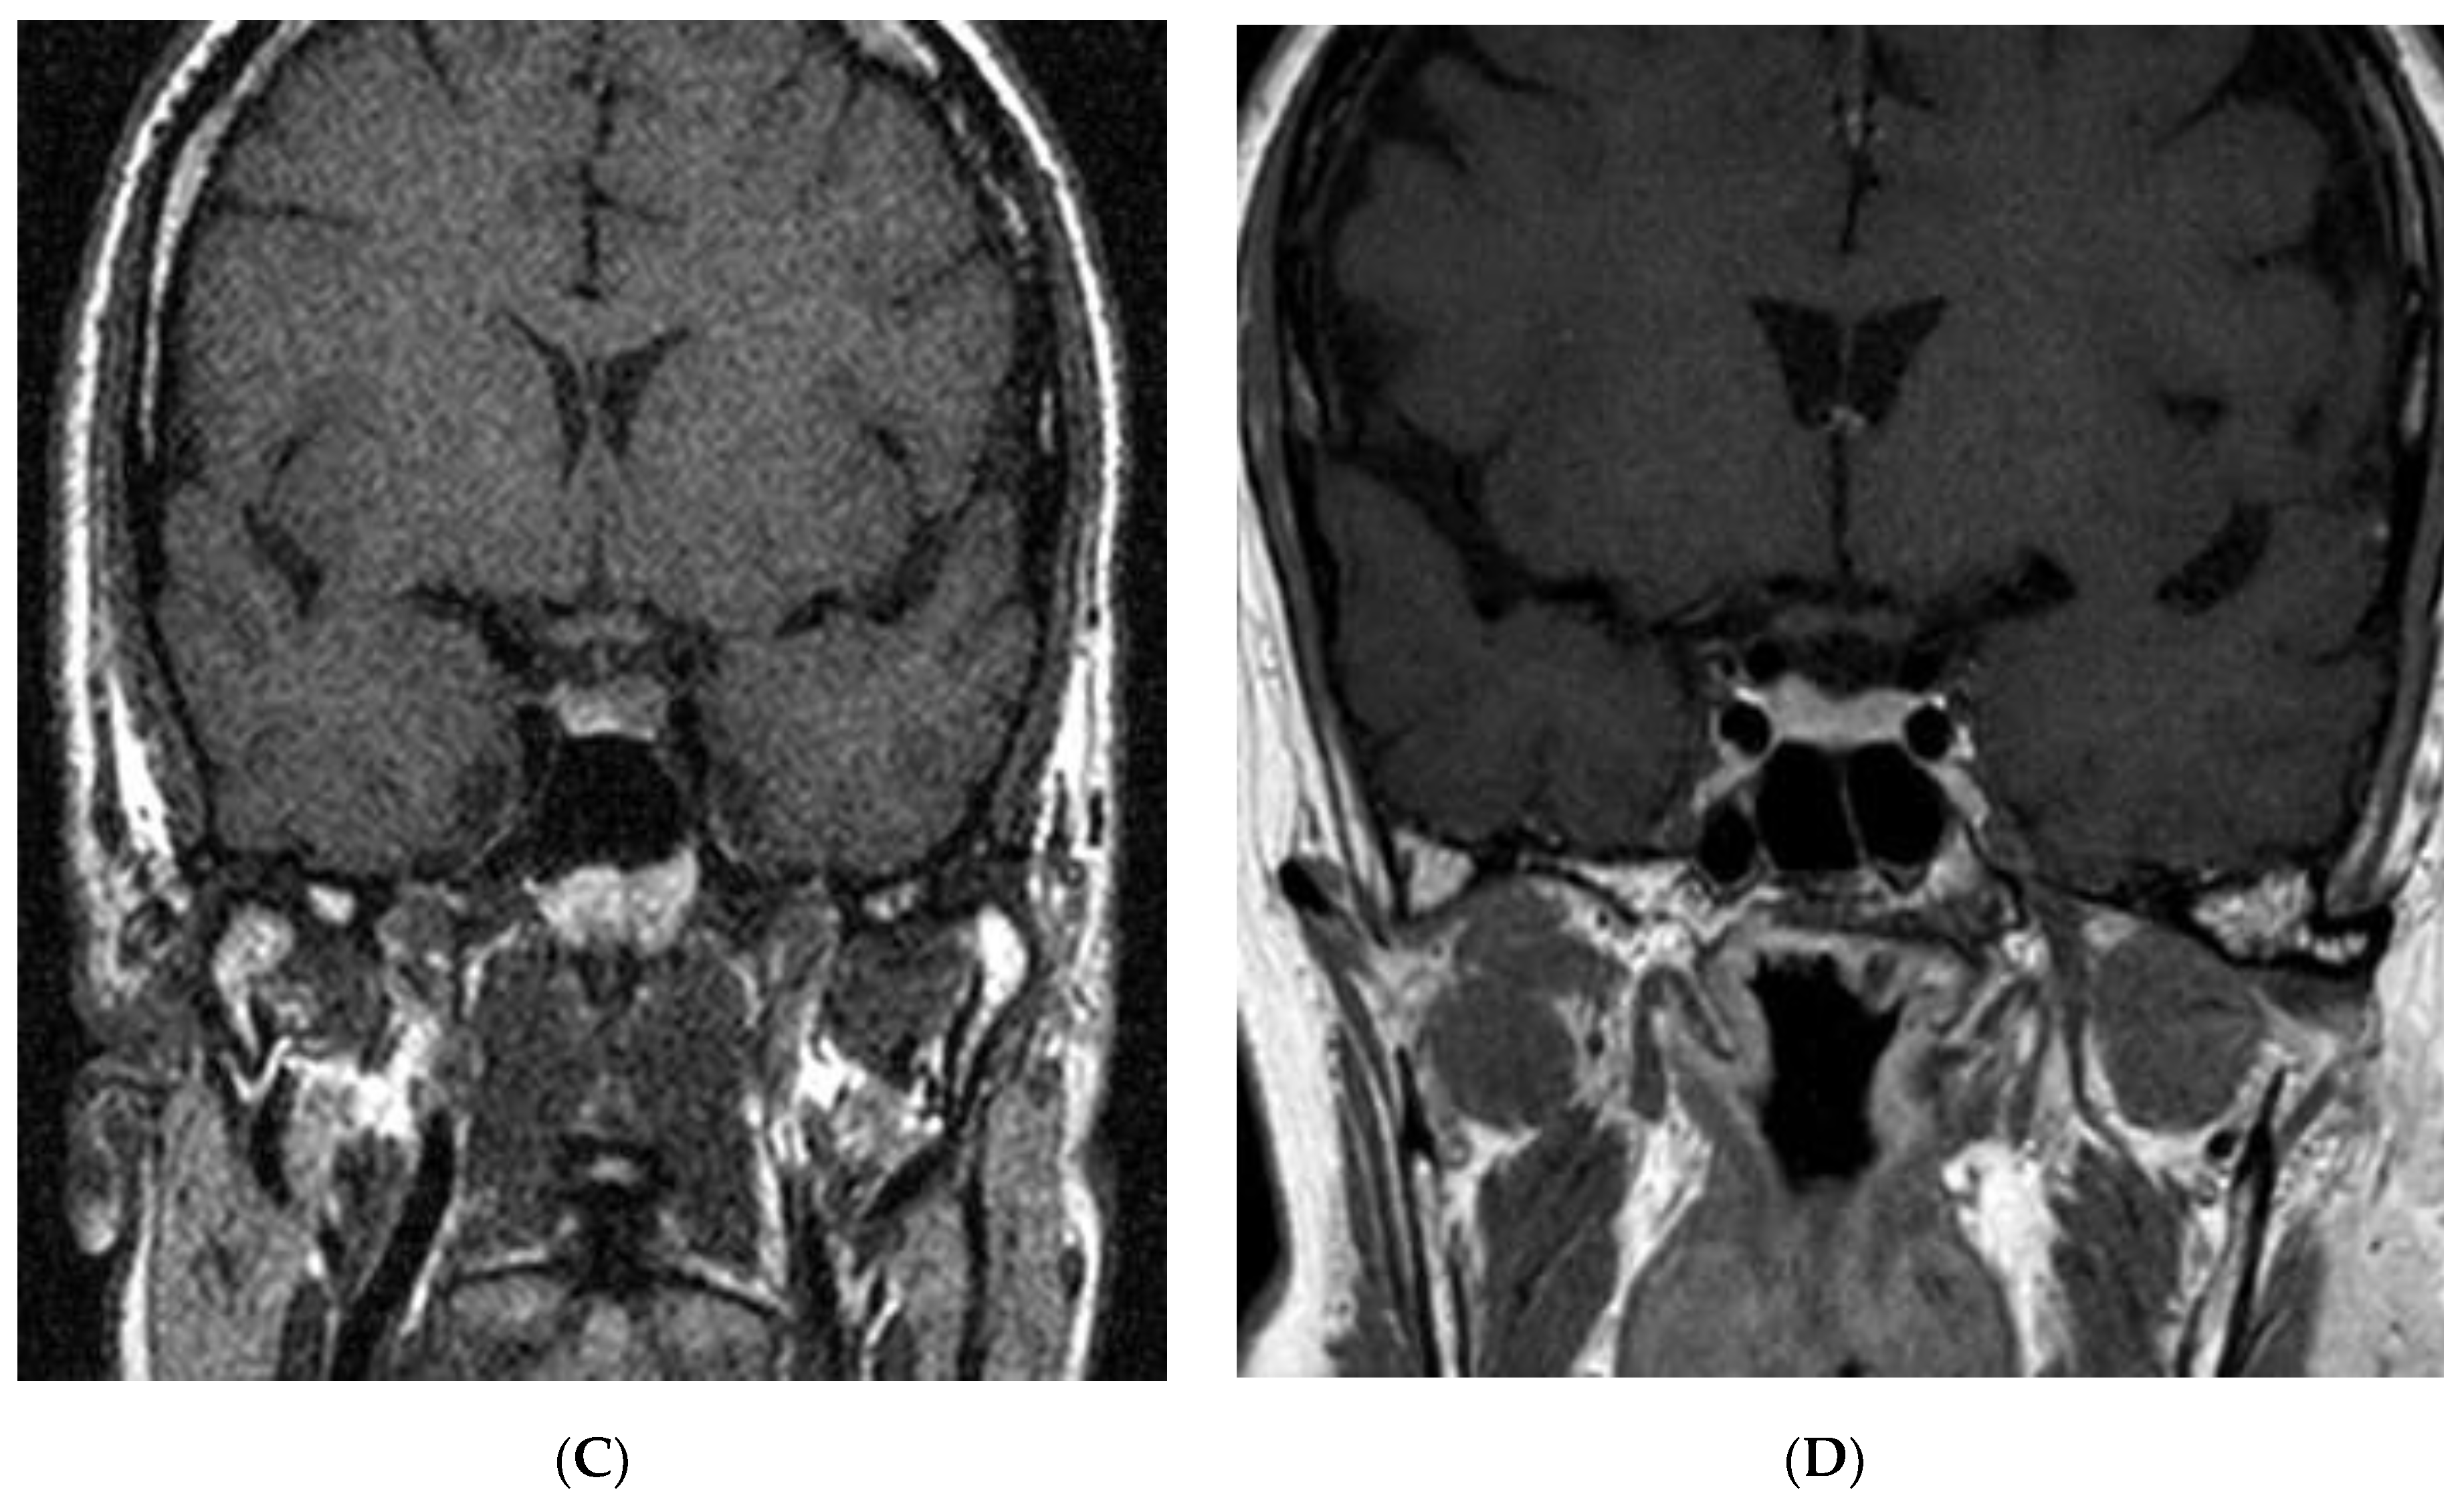

2.3. Acromegaly

2.4. Prolactinoma and mixed tumors

2.5. Non-Functioning Pituitary Adenomas

2.6. Pituitary Apoplexy and Other Tumors in AIP Mutation-Positive Patients

2.7. Screening and Investigation of AIP Mutation Carriers